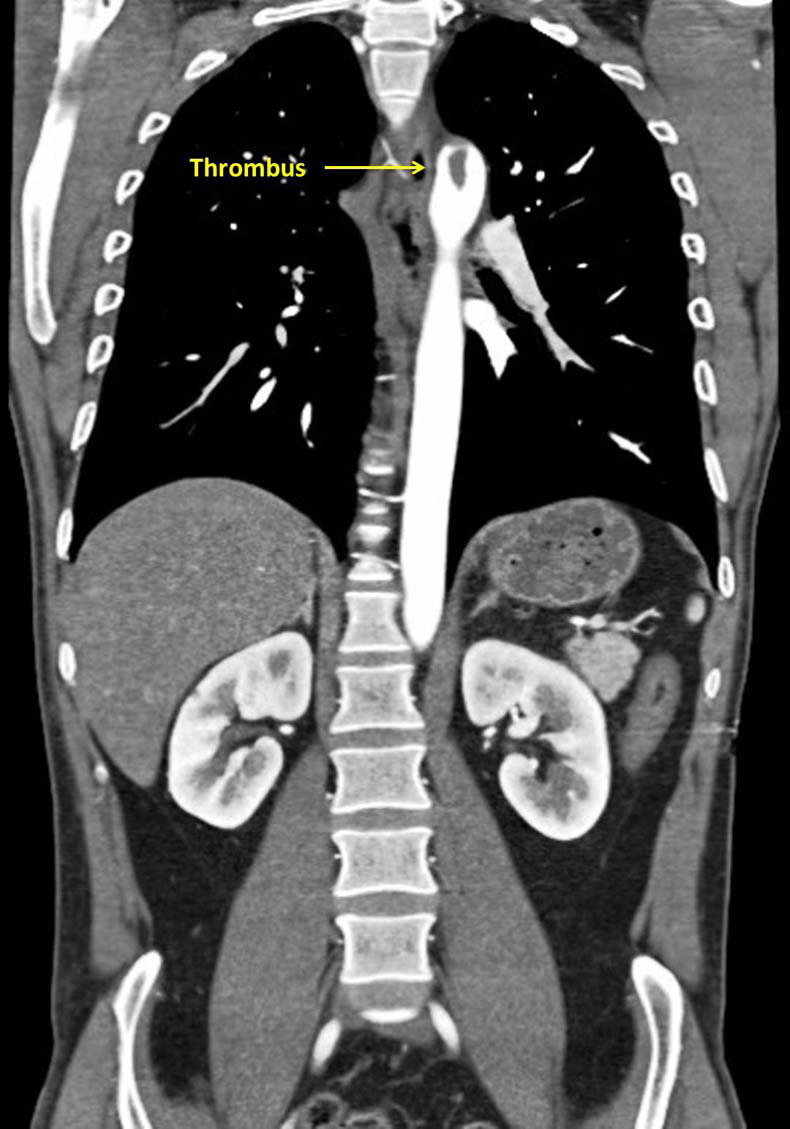

CT aortogram revealed a large, immobile thrombus fixed in the arch of aorta causing subtotal occlusion of the ostium of the left subclavian artery, with the rest of the aorta having no evidence of atherosclerosis or aortitis and the coronaries were normal (figures 1–3).

Figure 1 Coronal view of a large thrombus attached to the descending aorta at the origin of the subclavian artery.